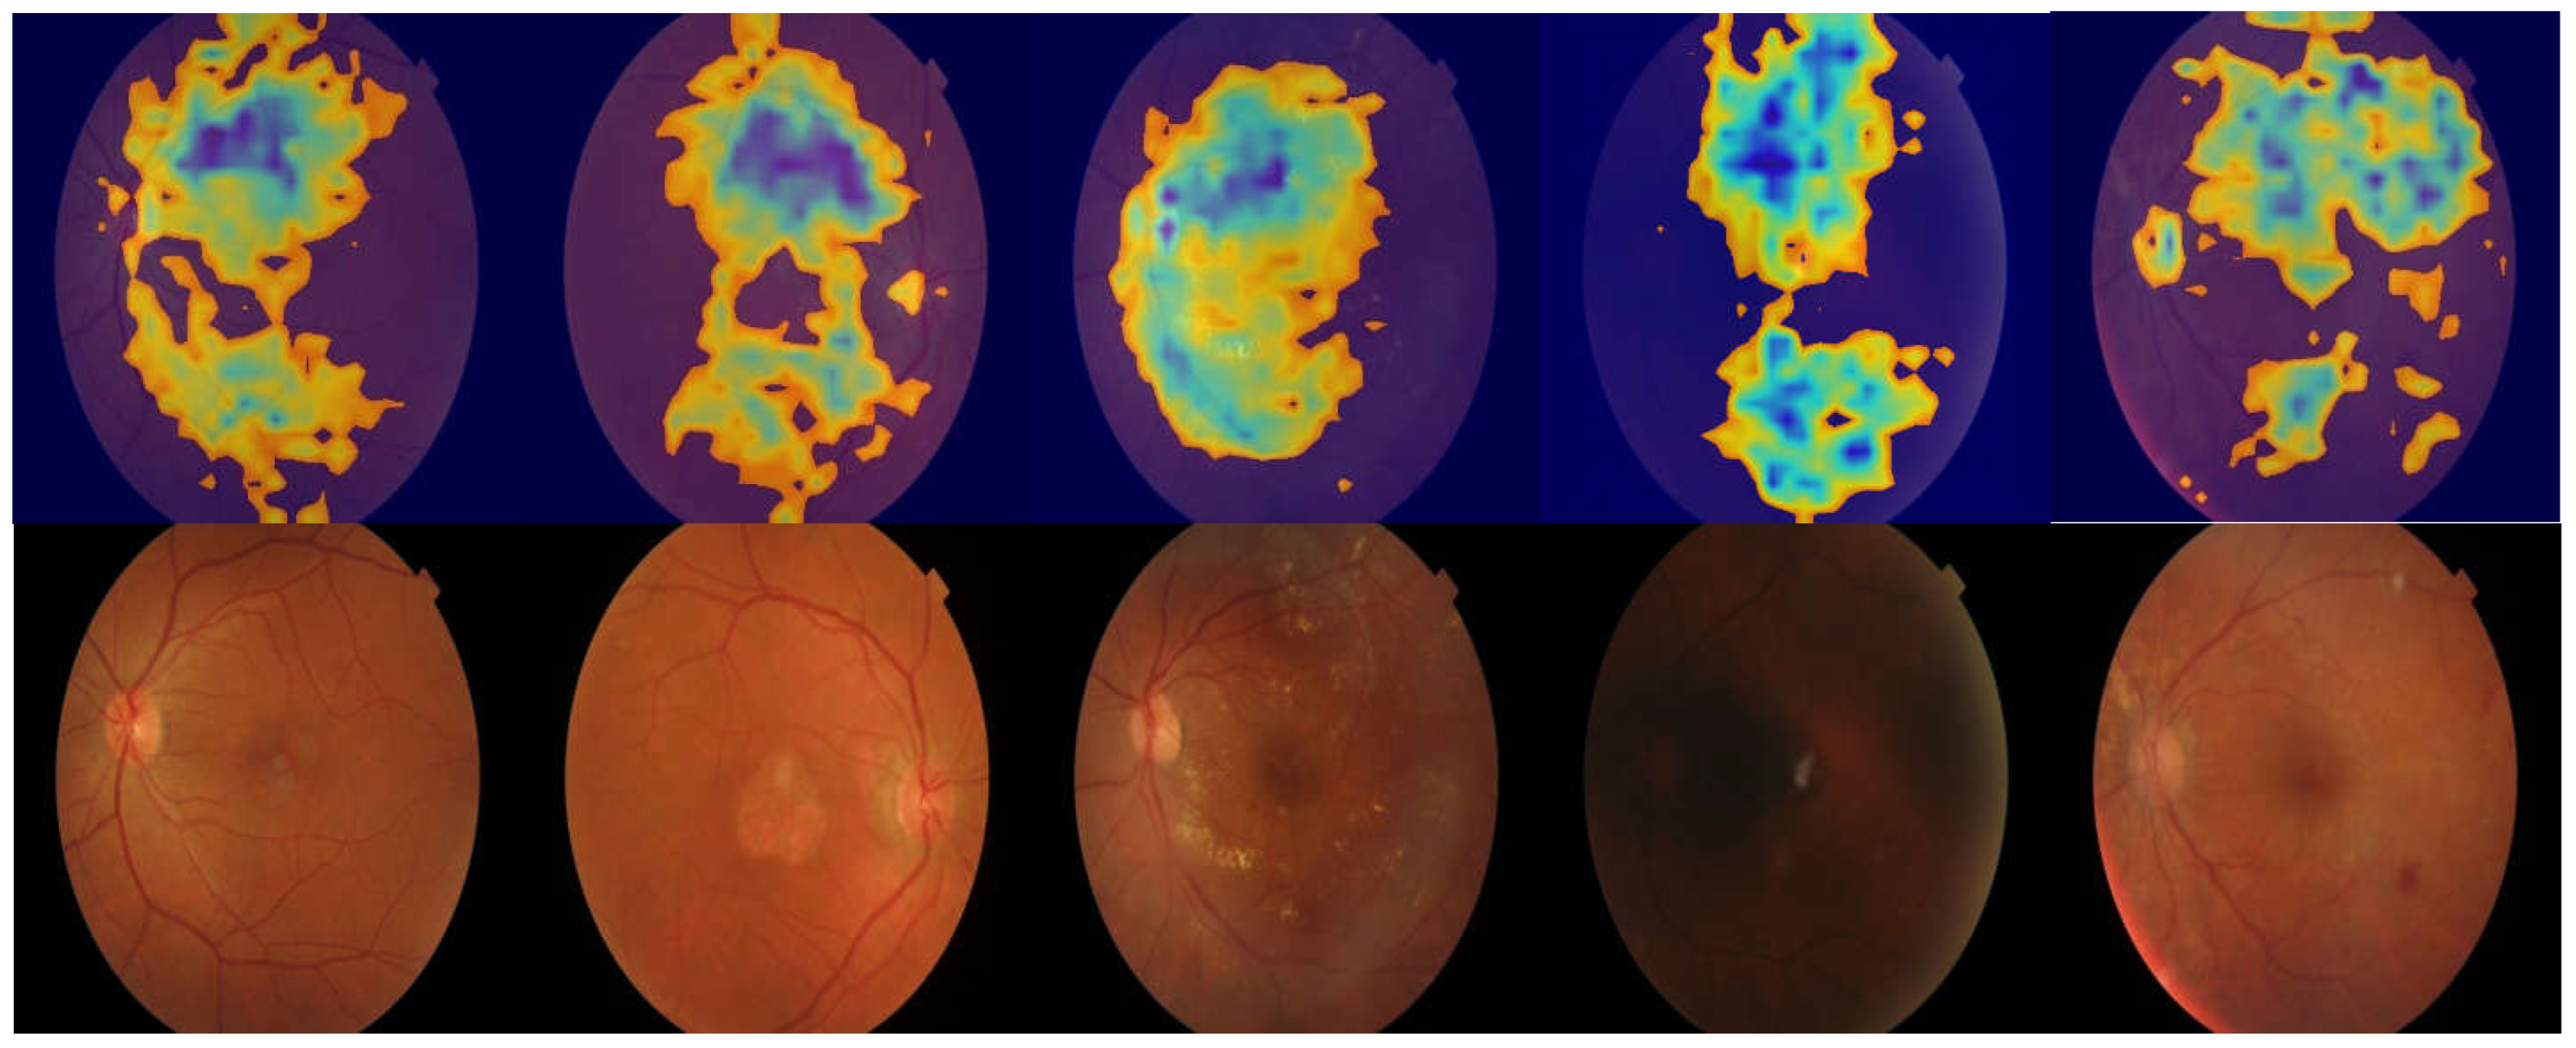

3.2. Region of Interest Visualization